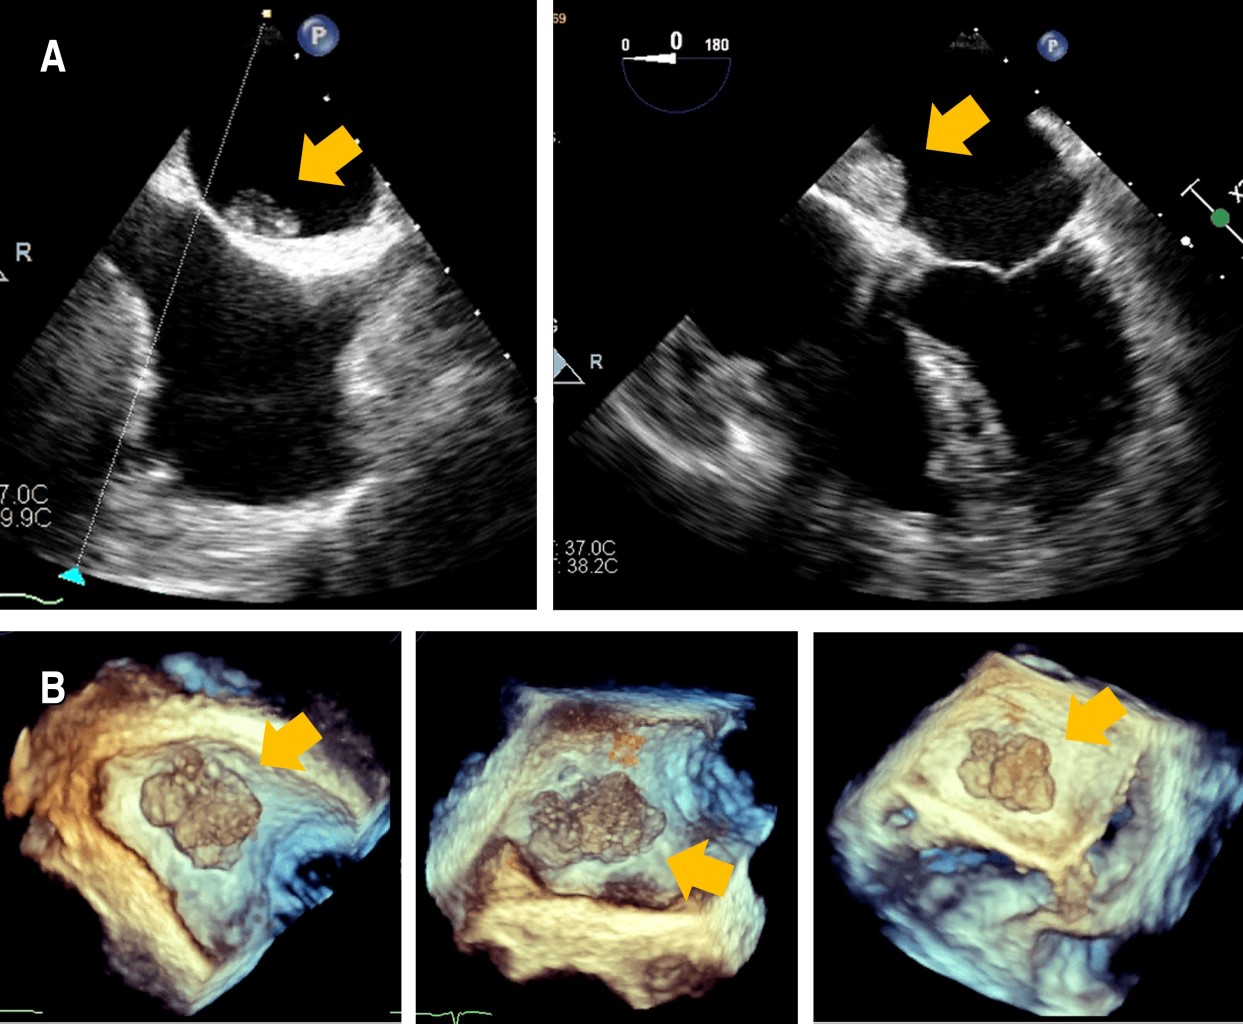

Figura 1